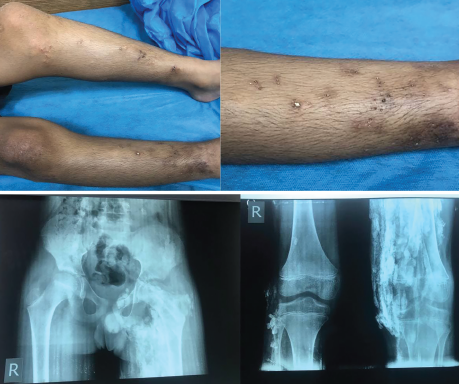

Rheumatic Diseases of Childhood: Juvenile Dermatomyositis with Calcinosis Cutis

These images depict a 14-year-old boy with a two-year history of proximal muscle weakness affecting both upper and lower limbs, and a skin rash affecting his face. He was diagnosed with juvenile dermatomyositis and developed calcinosis over both legs with skin infection and ulceration. Plain X-ray of both his pelvis and femurs showed reticular pattern calcinosis. He had a poor response to a infliximab.